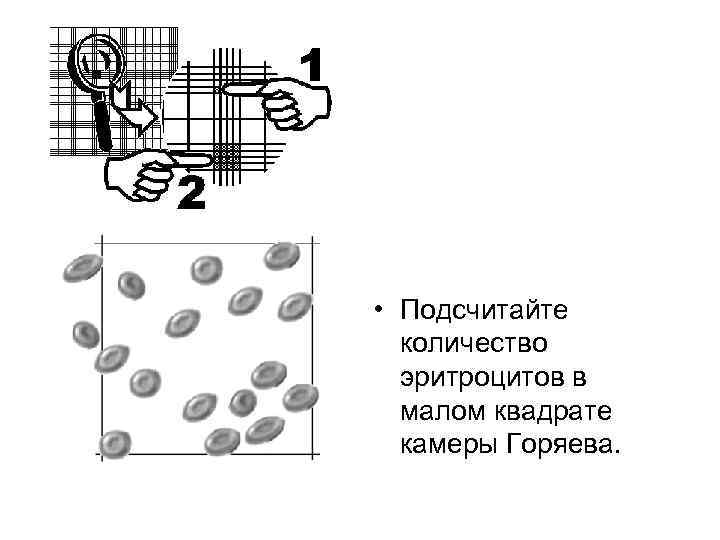

• Подсчитайте количество эритроцитов в малом квадрате камеры Горяева.

• Подсчитайте количество эритроцитов в малом квадрате камеры Горяева.